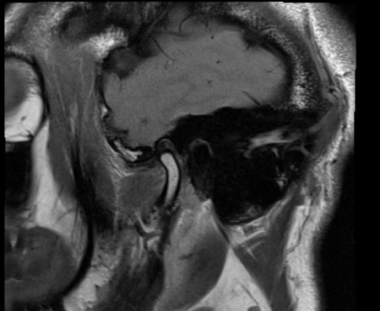

診断、治療計画の中ではMRI画像から軟骨が前方にずれているのが唯一確認出来ます。

私はこのことから顎関節のMRI撮影を行い患者さんの顎関節が正しい位置にあるかどうか?という確認を毎回しております。MRIを確認すると、顎関節の中の軟骨(関節円板)がずれている方に、このような症状が多いと思われます。